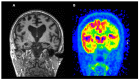

Alzheimer's disease is the most common form of dementia and is a significant burden for affected patients, carers, and health systems. Great advances have been made in understanding its pathophysiology, to a point that we are moving from a purely clinical diagnosis to a biological one based on the use of biomarkers. Among those, imaging biomarkers are invaluable in Alzheimer's, as they provide an in vivo window to the pathological processes occurring in Alzheimer's brain. While some imaging techniques are still under evaluation in the research setting, some have reached widespread clinical use. In this review, we provide an overview of the most commonly used imaging biomarkers in Alzheimer's disease, from molecular PET imaging to structural MRI, emphasising the concept that multimodal imaging would likely prove to be the optimal tool in the future of Alzheimer's research and clinical practice.